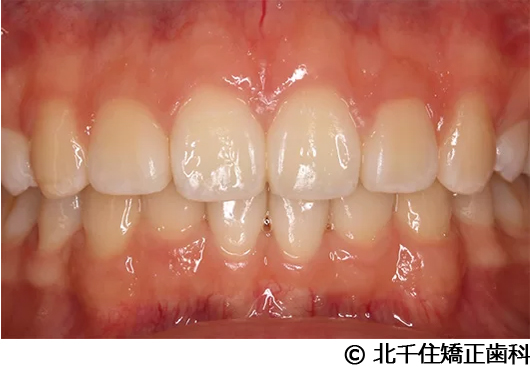

【症例2】上顎前突症

- 治療前

- 治療中

- 治療後

- 治療名

- 上顎前突症

- 費用

- 1,399,000円(税込)

- 期間

- 3年6ヵ月

- 治療回数

- 42回

- 通院頻度

- 1ヵ月ごと

- 年齢・性別

- 19歳10ヵ月・男性(初診時)

治療内容

主訴:出っ歯、口元の突出、横顔をきれいにしたい

骨格性の上顎前突、上下顎第一小臼歯4本及び上顎第二大臼歯を抜歯して矯正用アンカースクリューを併用してワイヤー矯正治療(セラミックブラケット)。

骨格性上顎前突に対し、抜歯および矯正用アンカースクリューを併用した矯正治療により歯列および咬合関係の調整を行った症例である。治療後は保定装置を使用し、歯列および咬合の安定維持を目的として定期的な経過観察を行っている。

※治療結果は個人差があります。

治療を行う上での注意点(リスク・副作用)

歯磨き不良に伴うカリエスや歯周病、顎関節症、歯根吸収など。